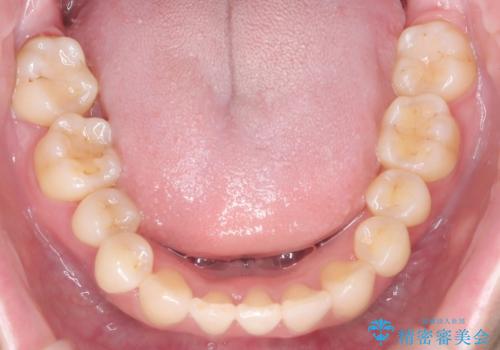

下顎前歯を1本抜歯し、歯列のスペースを確保。その後、インビザラインを用いて計画通りに歯を移動させ、噛み合わせも整えました。患者様の協力もあり、ゴムかけなどを適切に行い、予定通り1年で治療を完了。追加アライナーを使用することなく、計画通りに治療を終えることができました。患者様からは「思ったより早く終わり、仕上がりにも満足している」と喜びの声をいただきました。